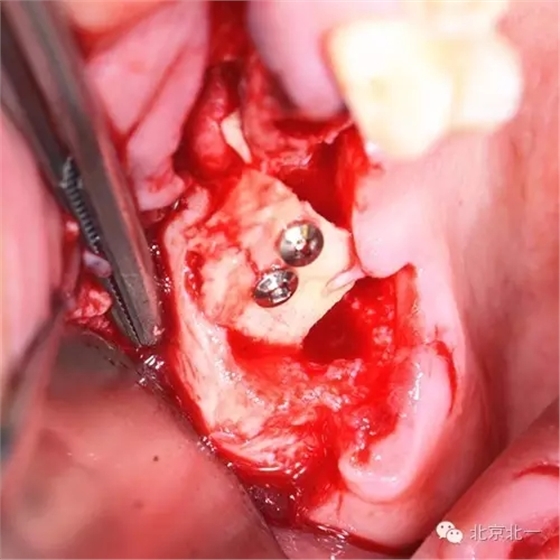

圖四:取骨區(qū),下頜智齒位置,取骨工具用超聲骨刀。

圖七:骨塊堅強內固定